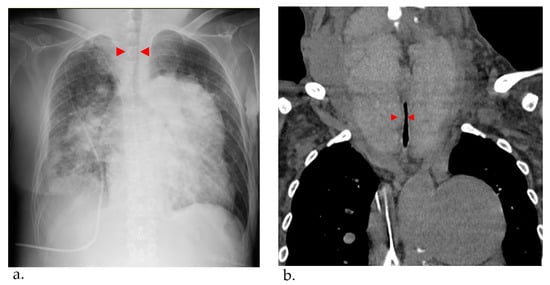

A Case of Giant Goiter Associated with Airway Stenosis Caused by Long-Term Intravenous Epoprostenol Therapy for Idiopathic Pulmonary Arterial Hypertension

Nishiura, K.; Nakazato, K.; Yokokawa, T.; Suzuki, Y.; Kurosawa, Y.; Wada, K.; Shimizu, T.; Oikawa, M.; Kobayashi, A.; Sugimoto, K.; et al. A Case of Giant Goiter Associated with Airway Stenosis Caused by Long-Term Intravenous Epoprostenol Therapy for Idiopathic Pulmonary Arterial Hypertension. J. Clin. Med. 2023, 12, 6359. https://doi.org/10.3390/jcm12196359